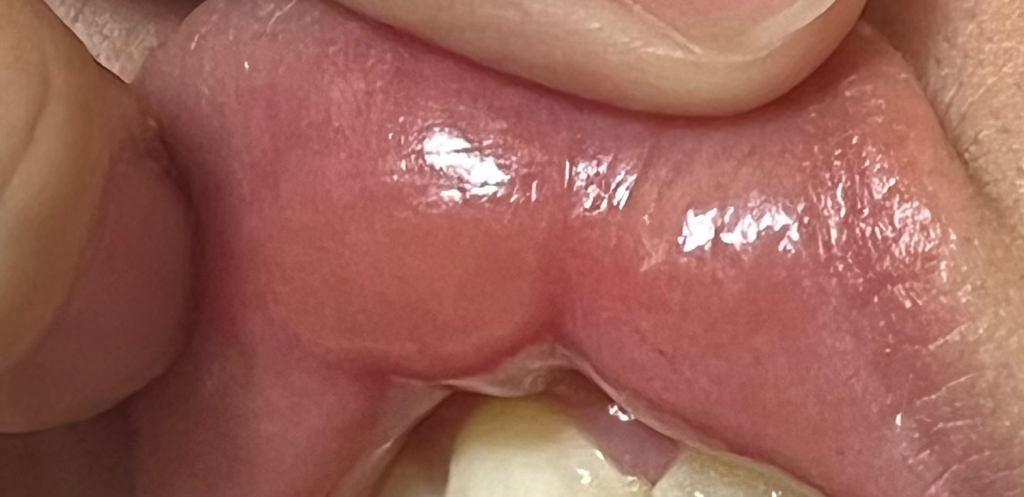

08년생 여학생입니다ㅜㅜㅜ 사진이 좀 웃기긴한데 제가 사실 한 1년전부터 가끔 음식을 먹고난후에 아랫입술이 가끔 빨갛게 부어오르는 증상이있었는데 그냥 바세린 바르고 지나갔거든요ㅜㅜ 근데 한 한두달전부터 원래는 붓고 말았던 증상이 이제는 없어지고 윗입술이랑 오른쪽 아랫입술 껍질..? 같은게 벗겨져서 다시 아물지도 않아요ㅜㅜ 각질인가 싶었는데 각질도 아니였구 그냥 말그대로 입술껍질이 벗겨져요 막 진짜 긁고싶을정도로 가렵구요ㅜㅜㅜ근데 오늘 저녁먹고 윗입술이 심하게 붓는거같아서 거울을 보니까 무슨 물집같은게 윗입술 가운데 크게 생겼고 그 바로 옆에 똑같이 작은게 이렇게 두개가 생겼더라구요..? 시간좀 지나니까 작은건 가라앉앗긴햇는데ㅜㅜㅜ 진짜 사진이 좀 웃긴데 느낌도 이상하고 진짜 저게 조금 크거든욬 ㅜㅜㅜㅜ 물집인가 싶어서 건드려봤는데 말랑말랑 하지도않고 약간 좀단단해요ㅜㅜ ㅈ좀 심해서 일단 자고 일어나서 아침에 괜찮아졌으면 좋겠네요ㅜㅜ 근데 껍질벗겨지는거랑 간지러운건 안사라져요.. 원래 바세린바르다보니까 괜찮아졌는데 이제는 바세린발라도 낫지도않고 간지러워요ㅜㅜㅜ 무슨 질병이 잇는건가여ㅜㅜ

• 1번 째 사진